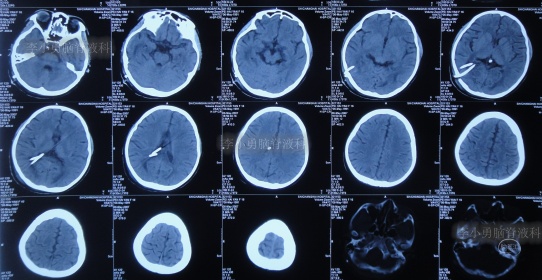

入院治疗18天即2020年4月29日,进行了脑室腹壁外引流术,头颅CT示脑室缩小,脑室内仅有1根管(图-21)。

图-21:2020年4月29日头颅CT

进行治疗3个月即2020年7月17日,脑积水已变完全清亮,且脑脊液化验各项指标正常,择期进行脑室腹腔分流术。

图-22:2020年7月17日

入院治疗100天即2020年7月20日,进行了脑室腹腔分流术。术后当天查头颅CT示脑室分流术后状态(图-23)。

图-23:2020年7月20日头颅CT

入院治疗109天即2020年7月29日康复出院,出院时:头晕呕吐已完全消失2月余,视物不清也变正常,睡眠也变好(图-24);出院时头颅CT示无异常(图-25)。

图-24:2020年7月29日

图-25:出院时头颅CT